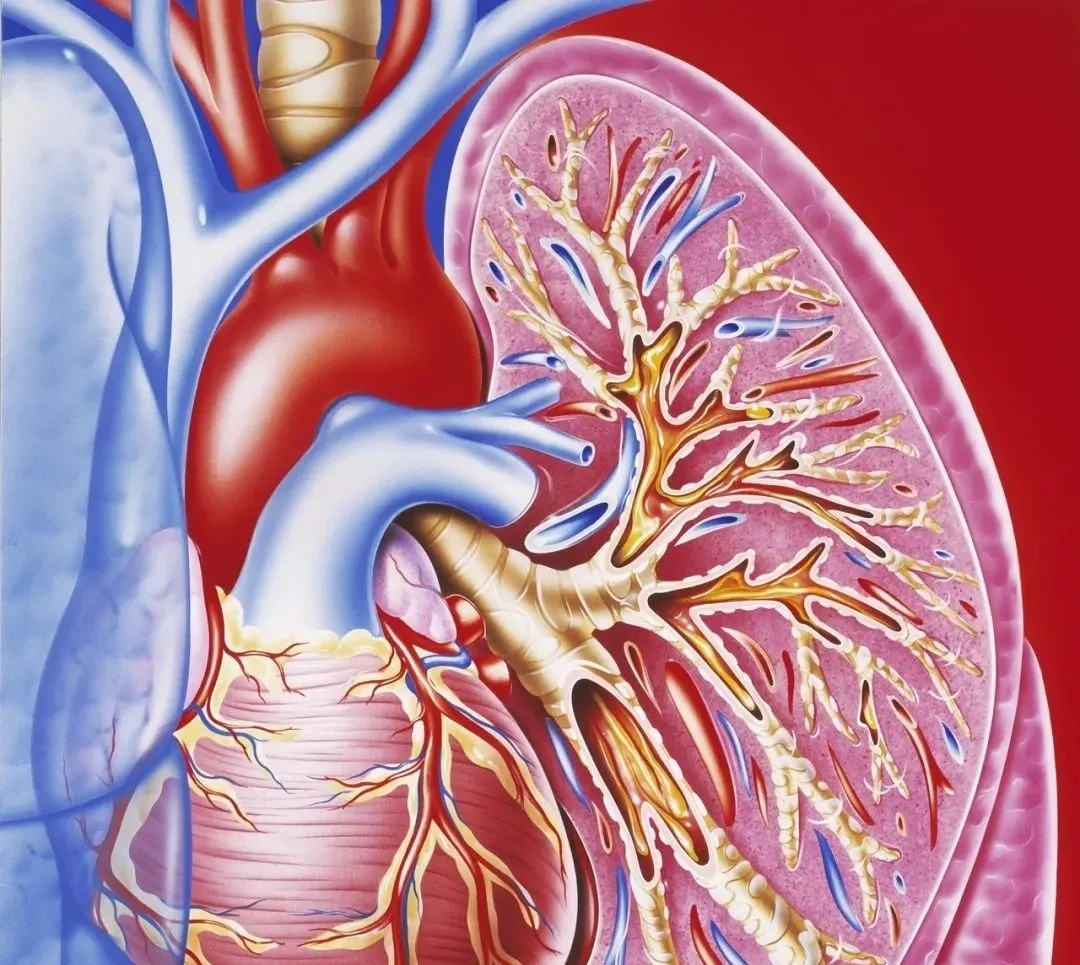

慢性(xìng)支气管炎(yán)是指(zhǐ)气管(guǎn)、支(zhī)气管黏(nián)膜及(jí)其周围组织的慢(màn)性非特异性(xìng)炎症。以慢性咳嗽、咳痰(tán)或(huò)喘息为(wéi)症状,每年(nián)持续发作(zuò)3个(gè)月(yuè)、连续2年或(huò)以(yǐ)上(shàng),部分病人可发展成慢性肺源性心脏病(bìng)、阻塞性肺气肿(zhǒng)。

慢性支气管炎分为单纯型和喘(chuǎn)息型。单纯型主要症状为咳嗽;喘(chuǎn)息型则除(chú)咳嗽、咳痰外,还存(cún)在(zài)喘息、伴有鸣哮音(yīn),喘鸣在阵咳、睡眠时加剧。